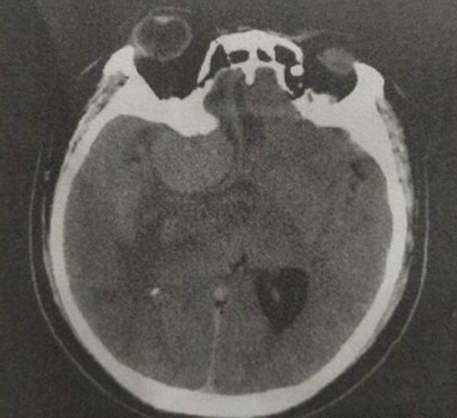

脑膜瘤因为原发位置不同,临床症状表现也不同。多有头痛,恶心,呕吐,抽搐等症状,严重可有肢体活动障碍。下图为ct,核磁影像